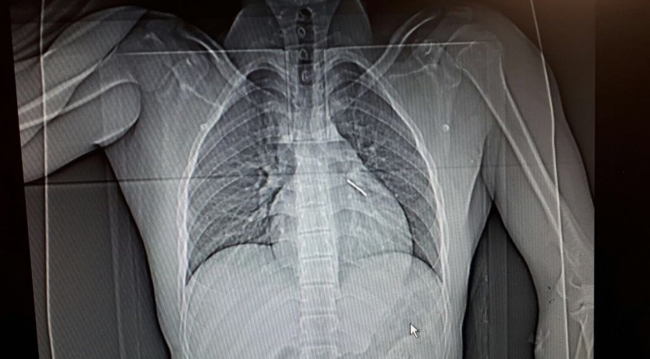

Göğsüne saplanan 5 santimetrelik çivinin yaklaşık bir santimetresi kalbine giren Bayır'ın sağlığına kavuşmasında personelin çabası da etkili oldu.

Bu sırada dengesini kaybedince elindeki havalı çivi tabancasıyla birlikte yere düştüğünü ve çivinin göğsüne saplandığını ifade eden Bayır, "Sol göğsüme saplanmıştı. İslahiye Devlet Hastanesine gittiğimde çivinin kalbime saplandığını öğrendim. Bu sırada beni Gaziantep'e sevk ettiler:" dedi.

"Çivi kalbin sağ yüzüne yaklaşık bir santimetre uzunluğunda girmişti. Geldiğinde zaten kanaması vardı. Hasta gelir gelmez ameliyata aldık ve kana müdahale ettikten sonra çiviyi çıkardık. Bu tip acil durumlarda koordinasyon çok önemli. Çok iyi koordinasyon sağlandı. Zaten hasta bize geldiğinde tüm bilgilere sahiptik. Bize gelir gelmez ameliyata aldık. Eğer koordinasyonda bir aksaklık olsa, en fazla 10 dakika daha gecikmiş olsa hastanın kurtulması mucize olurdu." AA